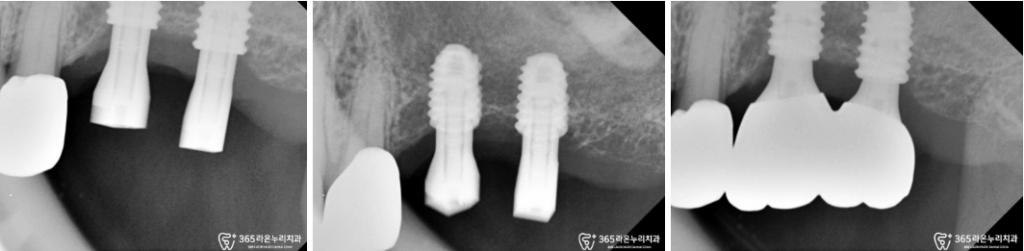

왼쪽 아래 앞니가 하나 결손되어 있는 것이

먼저 관찰되며, 다른 치아들도

흔들리고 상태가 좋지 않았습니다.

특히, 결손된 앞니 부위의

골도 심하게 내려가 있었습니다.

위턱 양쪽의 어금니가 모두 사라졌고,

오른쪽의 경우 작은 어금니 하나가

없는 모습입니다.

반대편에 있는 작은 어금니 하나도 심하게

파절되어, 코어 + 크라운을

진행해드리기로 결정했습니다.

아래턱 역시도, 치조골이 많이

내려가게 되면서 치아 뿌리쪽이

많이 드러나고 있었습니다.

엑스레이를 보시면 전체적으로

치아 뿌리가 드러날 정도의

골소실이 일어나 있는 것을

더욱 명확하게 확인할 수 있었는데요.

보시는 것과 같이

잇몸뼈가 뿌리 끝까지 녹아

더이상 치아를 지지하지

못하고 흔들리고 있었는데요.

이처럼 전체적으로 치아의 상태가 좋지

않았던 곳들은 발치 후 임플란트 식립 및

뼈이식 치료를 진행하기로 결정하게 되었습니다.